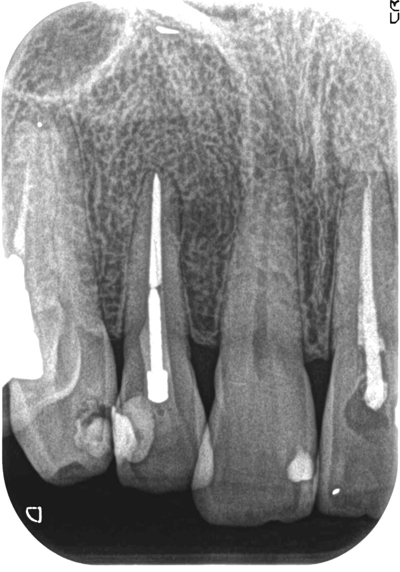

症例2【40代男性】右上側切歯の歯髄壊死。根管内も殺菌・消毒を約4ヶ月間行うことにより、病巣はほぼ消失し、硬線が明瞭に見える。

治療前

治療後(9ヶ月後)